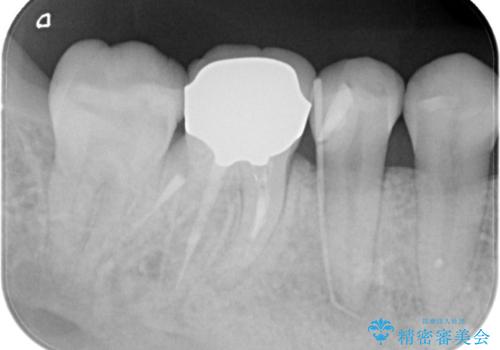

奥歯の被せ物のやり直し 精密根管治療